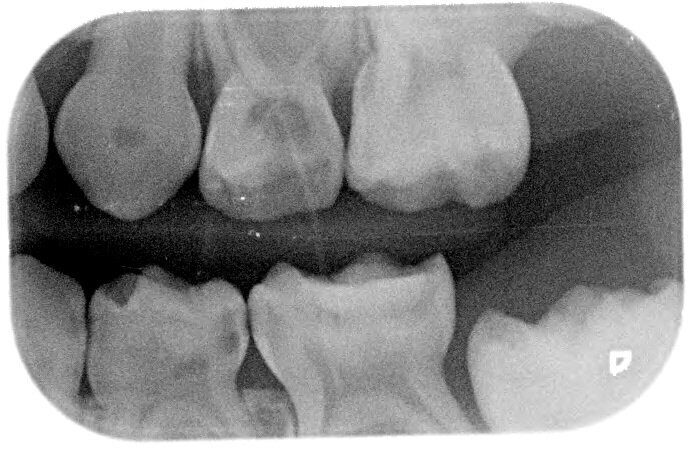

Het eerste kind waarbij wij NRC toepasten was 6 jaar. Op de bitewings werden cariëslaesies bij alle vlakken van de aangrenzende melkmolaren gediagnosticeerd. Met de ouders werd besproken wat onze plannen waren. Zij gingen hiermee akkoord. In de volgende zitting werden de 8 vlakken beslepen (afbeelding 1a-b). De behandeling verliep probleemloos en werd goed geaccepteerd. Maar in het vervolgtraject hebben we steken laten vallen. De voorlichtende communicatie gebeurde hoofdzakelijk traditioneel. De terugkomtermijn besloeg een paar keer achter elkaar een interval van bijna een jaar. Daar verander je geen gedrag mee. De verslaggeving ontbrak een aantal keren. Bijna 6 jaar later werd geconstateerd dat er veel plaque aanwezig was. De wisseling had inmiddels plaatsgevonden. Restauratief of chirurgisch ingrijpen is sinds NRC werd toegepast niet nodig geweest en de bitewings vertonen geen cariësactiviteit (afbeelding 2a-b). Ook waren geen sealants noodzakelijk geweest.

Afbeelding 1a. Beslepen melkmolaren in de bovenkaak (NB het verdient aanbeveling de distale vlakken schuiner te beslijpen dan de mesiale vlakken in verband met de toegankelijkheid voor de tandenborstel).

Afbeelding 1b. Beslepen melkmolaren in de bovenkaak (NB het verdient aanbeveling de distale vlakken schuiner te beslijpen dan de mesiale vlakken in verband met de toegankelijkheid voor de tandenborstel).